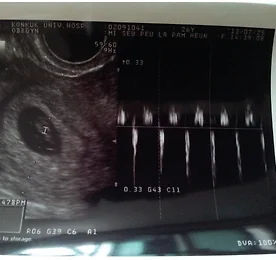

도림천 벚꽃길 도림천역 앞 개천으로 이어지는 벚꽃길 더보기 우제 아빠의 초음파 이야기 '우제' 아빠 이야기(2) 정확한 임신여부를 확인하고자 산부인과를 찾았다. 초음파로 임신여부를 확인하는데... 뭐가뭔지... 초음파 사진보기 GS : 태낭(아기집)HC : 아기 머리 둘레 수치AC : 아기 배 주위 길이BPD : 머리의 가장 지름 길이FL : 아기 허벅지 길이APTD : 아기 복부, 배의 두께를 측정한 수치FTA : 태아 복부 단면적TTD : 아기의 옆구리 폭CRL :아기 머리에서 엉덩이 까지의 길이 (8~10주사이에 측정 가능함)OFD : 태아머리 뒤꼭지~앞꼭지 직경APD : 앞뒤직경HR : 심장 박동수FW : 태아 몸무게AFI : 양수지표EDD : 출산 예정일GA : 추정되는 임신 주 수+마크 : 초음파 좌,우, 중앙에 있는 2개의 +마크는 2개의 + 사이의 길이를 측정날짜 : 초음파.. 더보기 중국 최고 검색엔진 바이두(baidu)에 홈페이지 검색 등록하기 중국 최고의 검색사이트 하면 바이두(Baidu)를 손꼽을 수 있다. 중국하면 언어를 모르는데 어떻게 하는 질문이 나올것이다. 글로벌(Global) 검색사이트는 다르다... 일단, 바이두(Baidu)에 방문하자... ▶ 바이두(Baidu) 홈페이지 검색등록 바로가기 ◀ URL 부분에 홈페이지 또는 블로그 주소(URL)을 기입하고, 밑 부분에 이미지 텍스트를 기입 후 클릭하면 검색등록 완료... 이제, 중국 최고의 검색사이트에 홈페이지 또는 블로그를 쉽게 등록해 보세요... 더보기 이전 1 ··· 58 59 60 61 62 63 64 65 다음